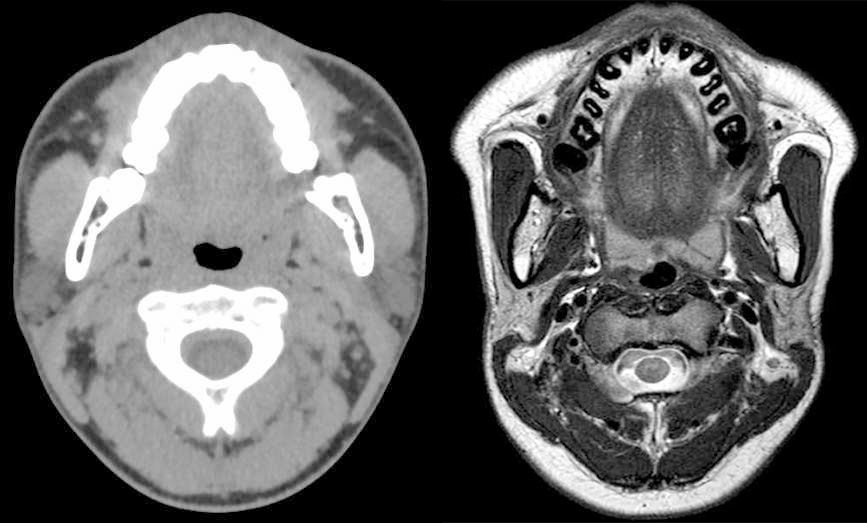

画像診断機器の急速な進歩により、頭頸部領域の複雑な解剖を画像診断で詳細に評価することができるようになり、質的診断や治療方針に役立つ情報を提供できる機会が増えてきました。頭頸部領域では空間分解能が高いCT、組織コントラストに優れるMRI、機能画像であるPETが主たる画像診断装置として用いられます。放射線科診断医は症例毎に適切な撮像法や撮像範囲を選択して、病変をより明瞭に描出できるように努めています。近年、頭頸部癌では機能温存治療が重要視されているため、治療前の画像診断で病変の広がりを診断して臨床病期を正確に判定することにより、症例毎に適切な治療法や治療範囲を決定する必要があります。また画像診断で良悪性診断、組織診断が可能になれば、適切な治療方針を迅速に決定することができ、治療開始までの期間を短縮できます。このように、頭頸部領域の診療において、画像診断は必要不可欠なツールになっています。

(左:CT画像、右:MRI画像)